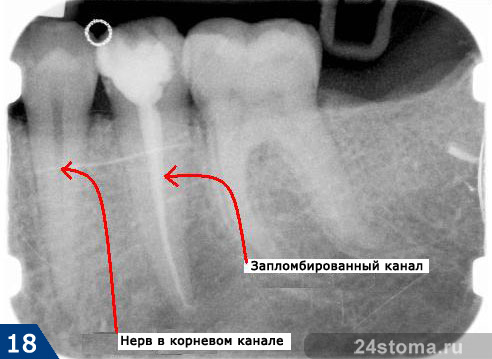

вот так выглядит запломбированный канал в зубе. Я бы на вашем месте сходила в другую клинику (если вы конечно не в платной делали, они хоть какую то гарантию дают, гос.клиники гарантию дают только на платные пломбы))

Ну у меня он так выглядел до этого лечения. После – я сама удивилась и не поняла, что она мне там наковыряла. Не поленюсь поеду отзыв напишу как– нибудь это гос.стоматология на Комсомольском 22, врач Бородина Анна Алексеевна ◊ Писать ироничные ответы на агрессивные выпады вместо того чтобы послать - тернисный путь самоконтроля исключительно воспитанных людей) Счастье - черта характера. |